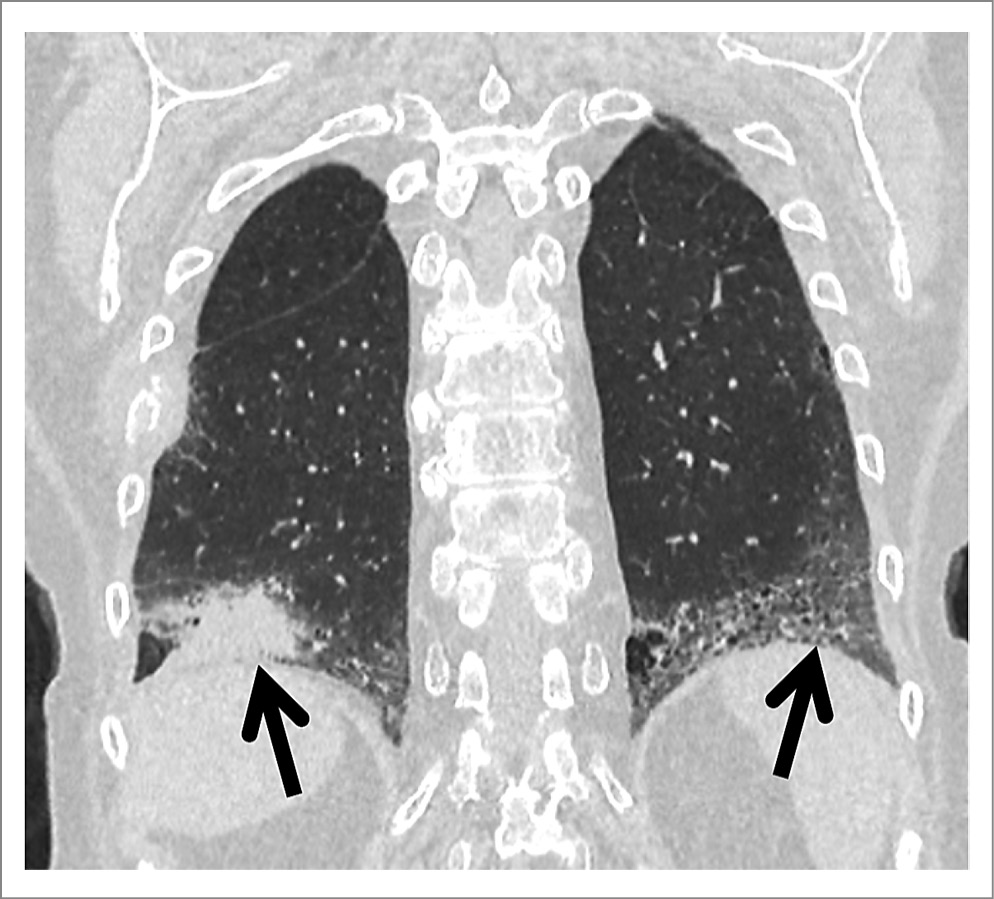

При КТ органов грудной клетки (ОГК) обнаружено образование нижней доли правого легкого размерами 55×40 мм с неровными нечеткими лучистыми контурами. В верхней доле правого легкого визуализировались два кольцевидных очага размером 4,5 мм. В нижних долях обоих легких, субплевральных отделах верхних долей и в средней доле справа определялись участки формирования сотового легкого. Медиастинальная лимфаденопатия. Деструкция VII ребра справа, вероятно, вторичного характера. При предыдущем исследовании от 25.04.2023 очаговые изменения не выявлялись, имелись лишь проявления интерстициального поражения легких (рис. 2, 3).

Рис. 2. КТ ОГК. Визуализируются образование нижней доли правого легкого, участки формирования сотового легкого в нижних отделах обоих легких, деструкция VII ребра справа.